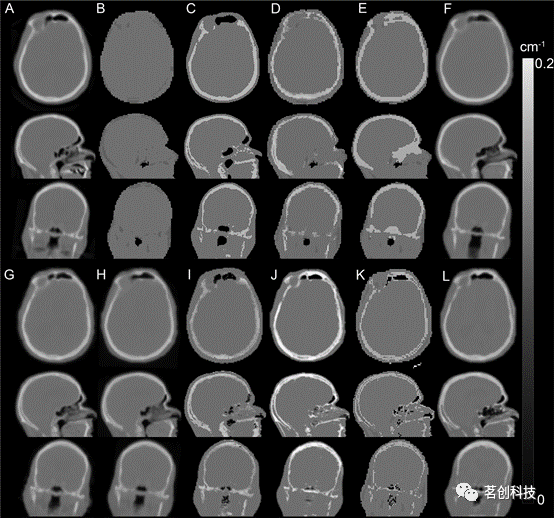

Ladefoged等人(2017)采用多中心337例脑PET/MRI和同日低剂量CT数据,对11种头部衰减图生成方法进行了评估。尽管这些方法在稳健性和异常值方面存在差异,但总的来说,所有测试的方法与基于CT方法的平均误差在5%以内。该研究表明,在正常解剖结构的成人大脑中提高MR(衰减校正)准确性的挑战已经达到了一个可接受的量化程度,这比PET成像中量化分析的可重复性要小(如图2所示)。

图2.基于磁头MR的衰减校正方法。用不同方法生成的衰减图:(A)CT,(B)Dixon,(C)UTE,(D)Segbone,(E)Ontario,(F)Boston,(G)UCL,(H)MaxProb,(i)MLAA,(j)Munich,(K)CAR-RiDR,(L)RESOLUTE。